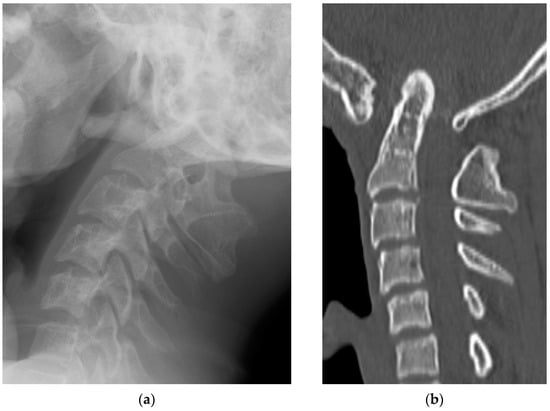

Radiological examinations demonstrated the abnormalities of the craniocervical junction and fusion of C2/3. Scoliosis in the cervicothoracic region was also confirmed. Computer tomography (CT) scans revealed the assimilation of the occiput with the atlas and posterior deviation of the odontoid process, which was invaginated into the foramen magnum (Figure 1). Magnetic resonance imaging (MRI) demonstrated severe ventral compression of the medulla oblongata and the spinal cord (Figure 2).

Figure 1. Preoperative radiographic images: (a) lateral X-ray view; (b) sagittal view of a computed tomography scan.